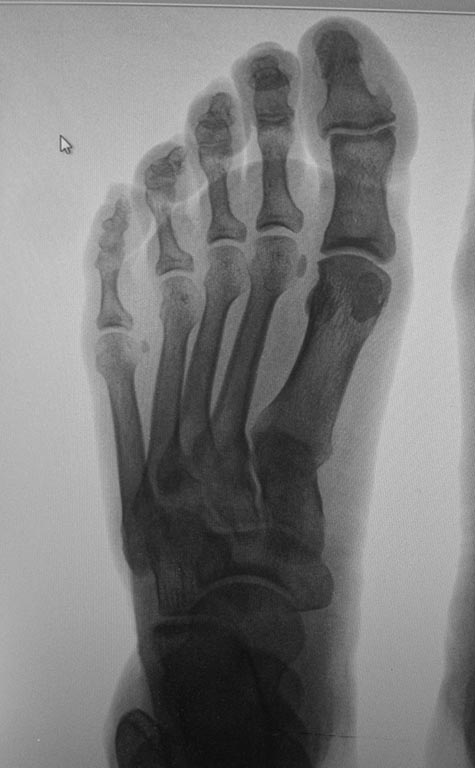

Обратилась женщина с жалобами на выраженную боль, натоптыши в области

проксимальных межфаланговых суставов V пальцев стоп.

У больной имеется деформация Тейлора ( угол М4М5 11.5 с двух сторон под

нагрузкой). В области пятого плюснефалангового сустава деформация. Боли,

гиперемии нет.

Достаточно ли в данном случае остеотомии пятой плюсневой кости с

нормализацией угла М4М5 и укорочением?